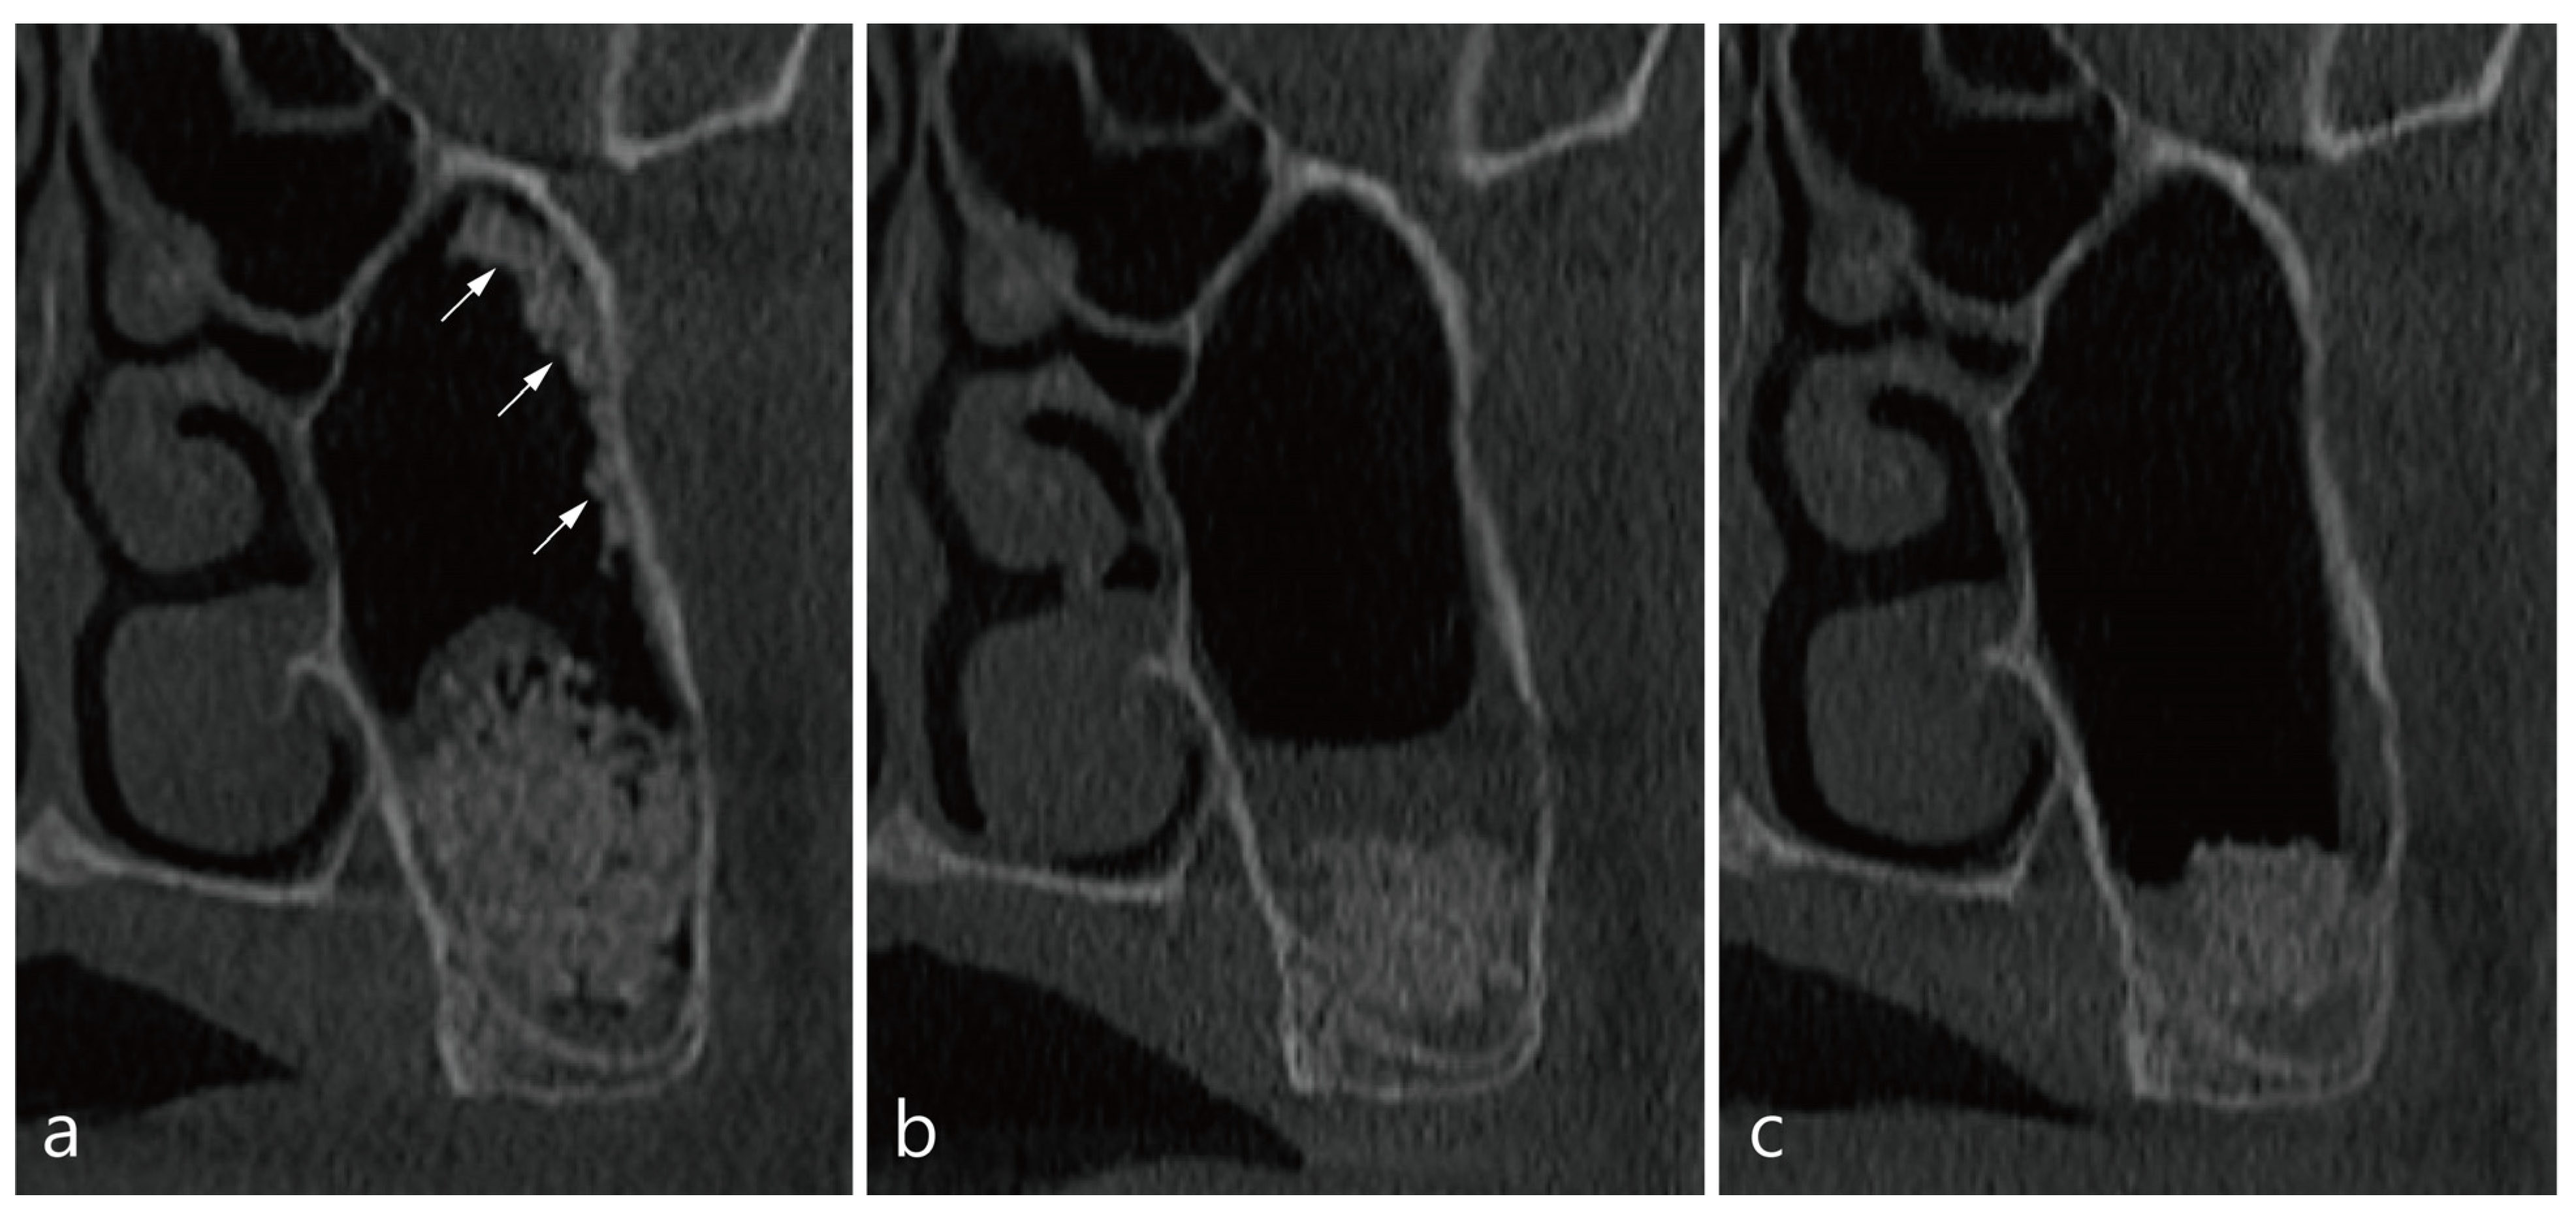

4. Case 2